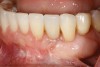

Figure 7  Radiograph of residual ridge defect in site No. 22.

Figure 7

The patient had no medical concerns and had a history of an implant placement in December 2002 when she was 25 years old. In February 2005, she presented with a mobile implant and an associated advanced peri-implantitis. Radiographic review at the initial examination demonstrated significant destruction of the dentoalveolar ridge around the implant as well as around the adjacent natural dentition. Emergency-based treatment involved surgical implant removal only and debridement of the infection (Figure 4 and Figure 5). Following uneventful healing, an advanced ridge defect was apparent at the edentulous site and moderate and advanced attachment loss noted at No. 22D and No. 21M, respectively (Figure 6 and Figure 7). This case demonstrates bone loss of two separate origins: lack of bone because of tooth agenesis and destruction of bone from inflammatory peri-implantitis.